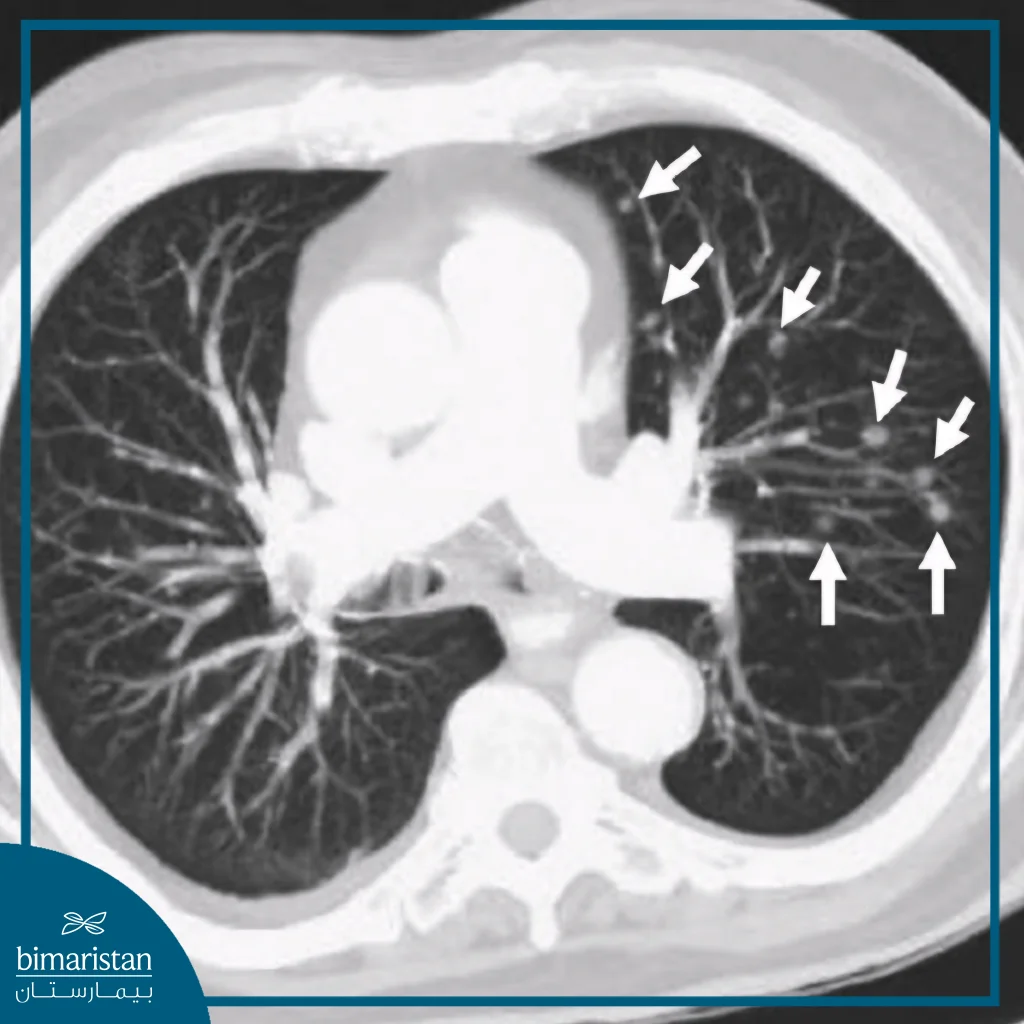

Pulmonary nodules are defined as small, round or oval-shaped areas that appear within the lung tissue, usually seen on chest radiographs or CT scans as distinct white spots that differ from the surrounding normal lung tissue, sometimes called “lung nodules” or “pulmonary nodules.” Any formation less than three centimeters in diameter is considered a nodule, while anything larger is classified as a pulmonary mass.

These nodules are relatively common, detected in approximately one-third of adults who undergo a CT scan involving the lungs, and are often found incidentally during examinations for other reasons without causing obvious symptoms. Despite the concern that seeing them on an image may cause, the vast majority of lung nodules are benign and non-cancerous in nature, but early detection of lung cancer in at-risk groups is recommended to ensure diagnosis in its earliest stages.

Pulmonary nodules are often discovered incidentally during chest imaging for another purpose, such as routine radiography or low-dose computed tomography used in lung cancer early detection programs. Once discovered, the doctor will evaluate the size, shape, border, and density of the nodule to determine the need for additional testing.

Computed tomography (CT) is the most accurate means of diagnosing these nodules, as it shows fine details of the internal structure and allows comparison of their size with previous images to determine whether they are stable or growing. Small nodules with smooth edges are often considered to be less dangerous, so periodic monitoring through imaging is often sufficient without immediate intervention. Nodules that exhibit abnormal characteristics or change in size over time require additional investigation, including blood and sputum tests to check for chronic inflammation or infection, or advanced imaging to assess the activity of cells within the nodule and assess the likelihood of malignancy.

Multiple nodules indicate the presence of more than one focus in the lungs, often reflecting a broader disease process such as diffuse inflammation, immunological diseases such as sarcoidosis, or, in some cases, cancerous spread from a tumor in another organ. These nodules are assessed by their distribution, size, and similarity between them, with a symmetrical and homogeneous distribution being more likely to be inflammatory or immunological causes, while nodules of varying shape and size raise the suspicion of metastasis.